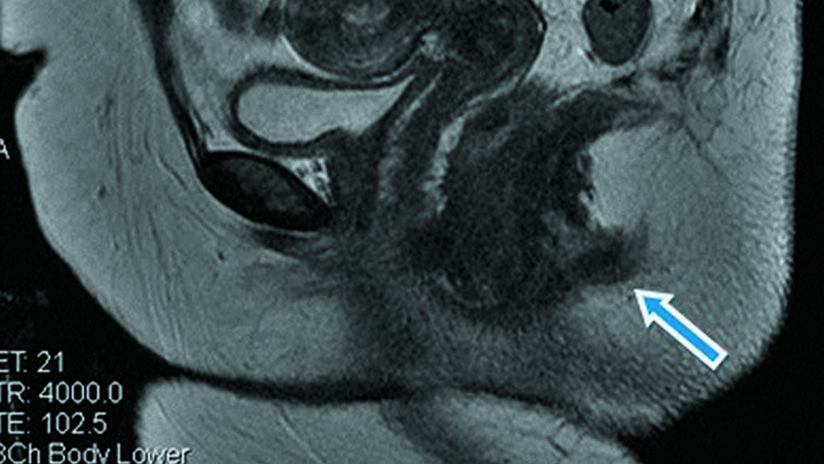

Los médicos dieron a conocer el hallazgo a través de una publicación en el Journal of Medical Case. El informe detalla que la paciente tenía una rara formación del tracto digestivo, lo que generó el segundo canal anal.

“La duplicación del canal anal es la malformación congénita del tracto digestivo más extraña. Cerca de 60 casos han sido descritos alrededor del mundo”, detallan en la investigación publicada por los médicos.